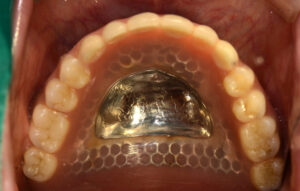

위 사진 속 환자분은 기존에 임플란트를 식립하여

그 위에 틀니를 고정시키는 방법인 오버 덴쳐를 사용하셨는데

임플란트가 편측으로만 식립 되어 있어 사용할 때마다 불편하다고 하셨어요.

원래는 양쪽으로 4개의 임플란트가 식립 되어 있었는데 임플란트 주변으로 염증이 발생하여 임플란트를 제거한 후 오른쪽 임플란트에만 고정시켜 사용하고 계셨다고 해요.

또한 상악에는 사용하시는 틀니에 불편함을 느끼지 못하고 유지력이 좋아 그대로 사용하시기로 하였어요.